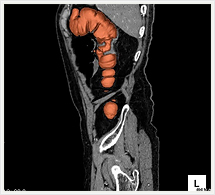

CTでは輪切り像の他にも立体的な画像(3D画像)を作成することもできます。そのためにはより細かくキレイな画像を撮影しなければなりません。当院では64列CTを導入しており、キレイな画像をより細かく撮影することができます。その画像を元に3D画像を作成することによって、より正確な手術のシミュレーションが可能になります。実際に手術をしたときの様子が、手術をする前に画像として見らます。外科系の手術には欠かせない技術となっておりますが、内科系でも血管内手術にも多く利用されております。

当診療放射線技術科では毎日各診療科に対して、その手術に最適な3D画像を提供しております。

以下にその3D画像を一部分紹介します。

下肢動脈